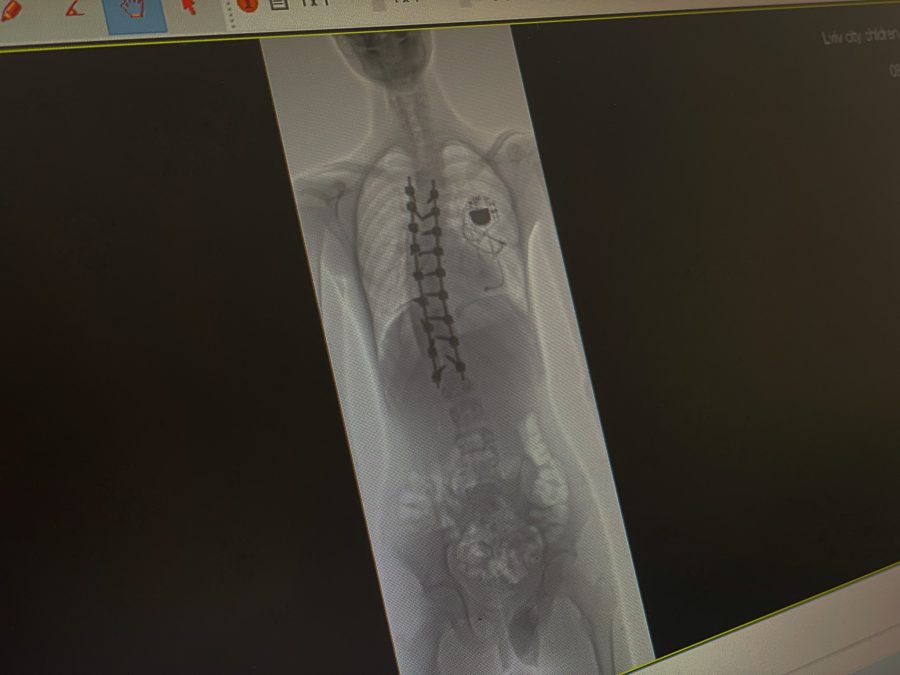

Хребет після операції. Фото: Дитяча Лікарня Святого Миколая

Операція проходила у кілька етапів. Спершу лікарі обережно відокремили спинний мозок Ярослава від навколишніх тканин – це був один із найнебезпечніших моментів. Далі встановили металеву конструкцію зі стрижнів і гвинтів, яка дозволила вирівняти хребет. У результаті викривлення вдалося зменшити з критичних 80° до 25° – це максимально можливий для безпеки спинного мозку показник. А завдяки ретельній підготовці вдалося уникнути кардіологічних ускладнень.

Один із провідних спінальних хірургів світу, американець Ізадор Ліберман, у Львові разом із лікарями дитячої лікарні Святого Миколая провів операцію 16-річному хлопцеві з кардіостимулятором і сколіозом найважчого, IV ступеня. Після операції викривлення хребта вдалося значно зменшити – з критичних 80° до 25°. Про це повідомили у пресслужбі медзакладу.